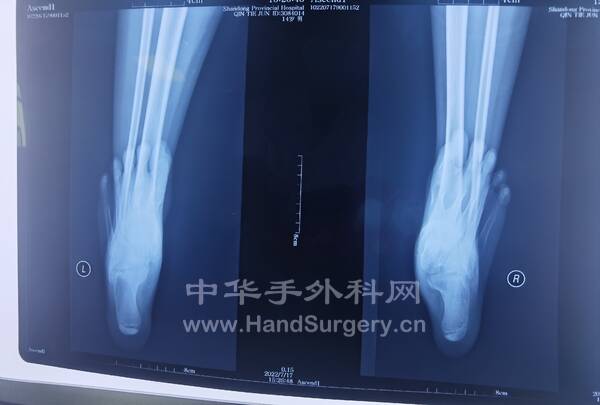

病例,男,19岁,身高196cm,体重100kg,左舟骨骨折术后1年,内置物折断

1.需手术患者一定注意体重问题,超正常体重较多的患者一定要晚负重,否则内置物易折断!